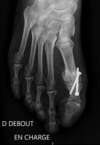

Il consiste à bloquer l’articulation métatarso-phalangienne douloureuse définitivement par des vis posées en croix, ou par une plaque vissée (cf images de radios ci dessous). Pour cela, l’ouverture de l’articulation se fait sous anesthésie de la jambe et du pied. L’opération dure moins  d’une heure.

arthrodèse metatarso phalangienne hallux par vissage en croix